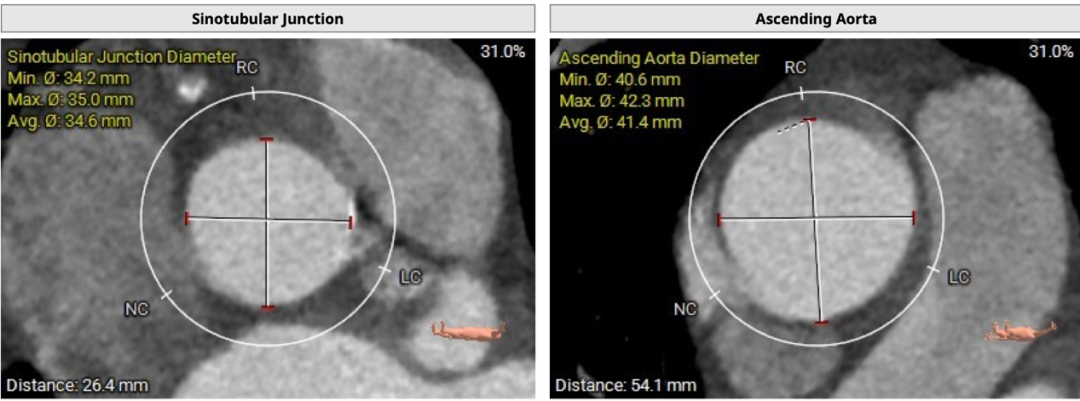

患者主动脉瓣三叶式,瓣叶基本等大,瓣叶稍厚,右无冠瓣瓣叶游离缘轻度钙化,瓣叶交界钙化有融合;主动脉瓣环周长折算直径约29.0mm:

双侧冠脉开口高度可,LCA 11.5mm, RCA 18.7mm;右冠、左冠及分支轻度钙化:

术中建议造影角度LAO 4°,CAU 6°(其它考角度如下图):

横位心,心室角度68°:

主动脉弓、腹主动脉及双侧髂总动脉见多发钙化: